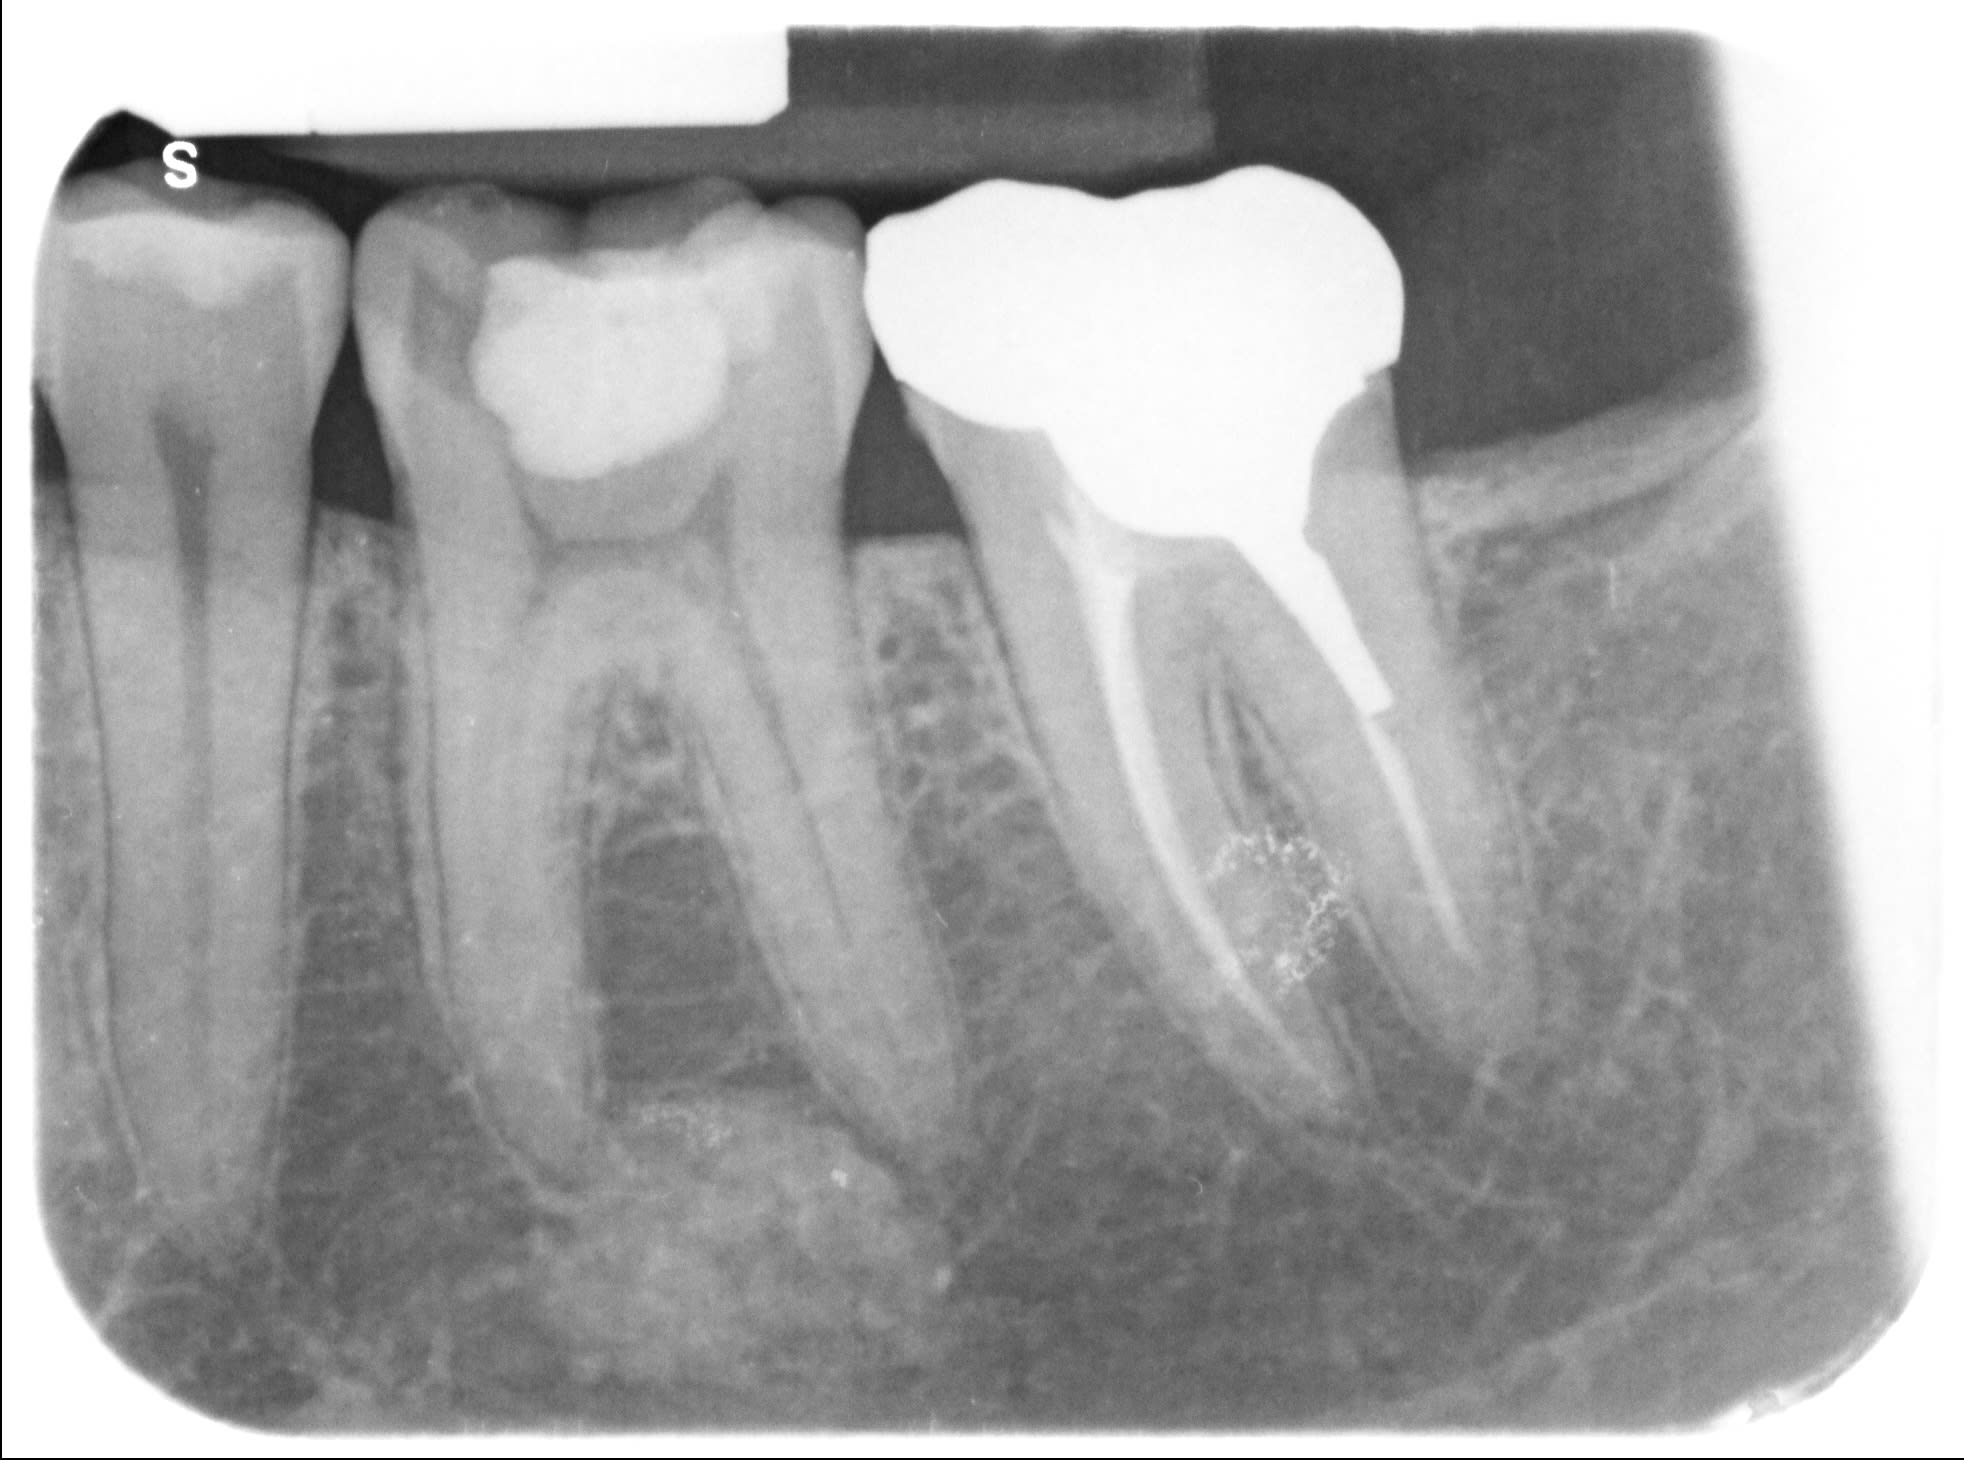

36 asymptomatique, je découvre cette image apicale avant réalisation d'un onlay.

Cémentome

Ostéite condensante?

J'aurais dit cémentome aussi !!

Si la vitalité est bien positive, qu'il n'y a pas de douleur à la pression ou à la percussion , ni à la palpation, je dirais que tu risques pas grand chose...

Je n'ai pas testé la vitalité... Je vais le faire mais je pense que je vais orienter quoi qu'il en soit chez le stomato, il y a un antécédent de maladie de Hodgkin je ne prends pas de risque